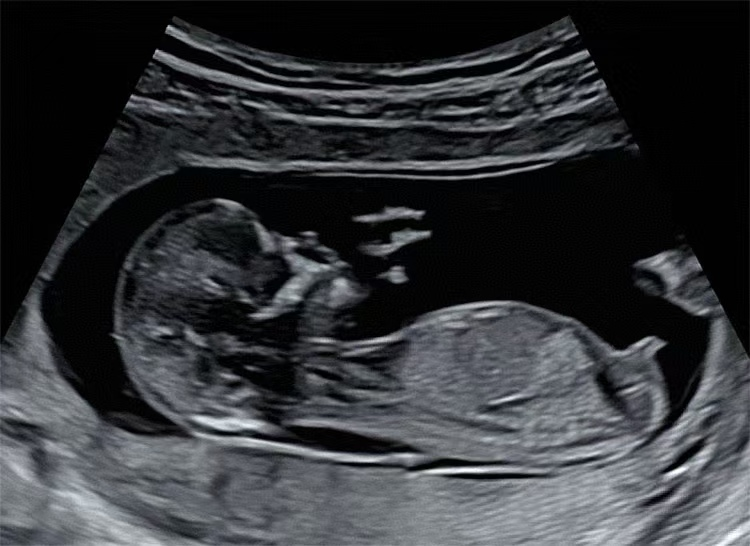

图3胎儿头臀长标准声像切面